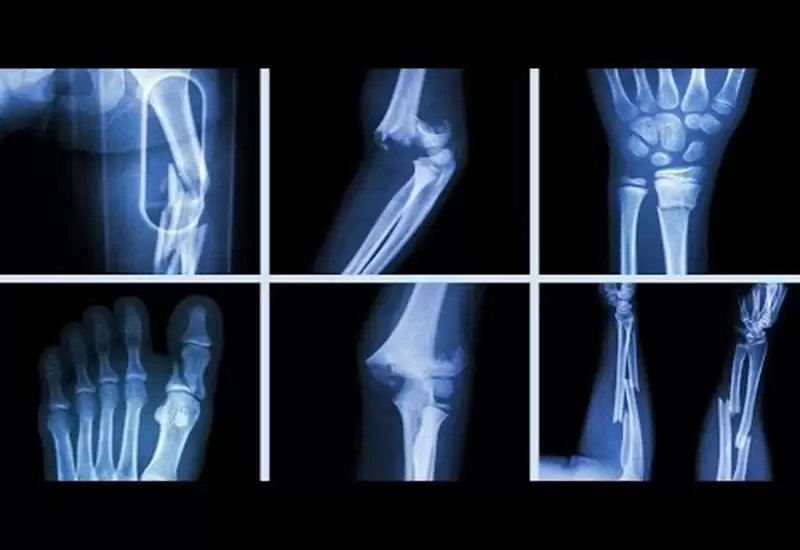

Gãy xương là tai nạn phổ biến có thể xảy ra trong sinh hoạt hàng ngày, lao động hoặc tai nạn giao thông. Việc sơ cứu đúng cách ngay tại hiện trường có vai trò quan trọng, giúp giảm đau, ngăn ngừa biến chứng và bảo vệ tính mạng người bị nạn trước khi được chuyển đến cơ sở y tế.

2. Phân loại gãy xương

- Gãy kín: Xương bị gãy nhưng không làm rách da

- Gãy hở: Xương gãy đâm thủng da, có nguy cơ nhiễm trùng cao